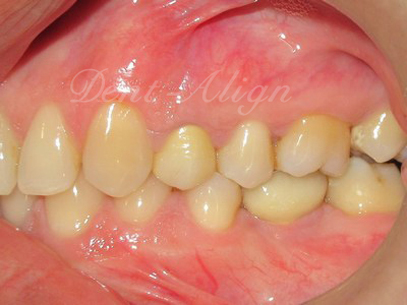

Diagnosis : The space present at the region of the missing tooth was inadequate to place a dental implant as the tooth present adjacent to the missing space had tipped into it.

a) Orthodontic phase : A micro screw orthodontic implant was used as a support to upright the tipped tooth.

b) Dental implant phase : After the space was created for the dental implant by orthodontics, dental implant with crown was placed.

Result : The missing tooth was replaced with an optimum sized implant and a good occlusion.